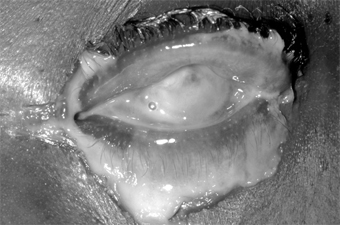

Conjunctival scarring is a frequent complication of trachoma and can destroy the ductules of the accessory lacrimal glands and obliterate the orifices of the lacrimal gland. These effects may drastically reduce the aqueous component of the precorneal tear film, and the film's mucous components may be reduced by loss of goblet cells. The scars may also cause distortion of the upper lid with inward deviation of individual lashes (trichiasis) or of the whole lid margin (entropion), so that the lashes constantly abrade the cornea. This often leads to corneal ulceration, bacterial corneal infections, and corneal scarring (Figure 5-2).

Figure 5-2

Figure 5-2: Advanced trachoma following corneal ulceration and scarring. Note the fly on the temporal aspect of the lower lid. The fly is a principal vector for trachoma.